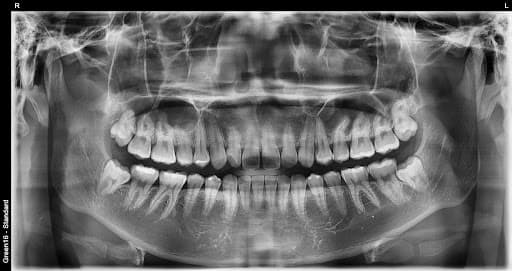

横生智齿

横向生长会挤压 相邻的牙齿

复杂的阻生智齿 - 即使深埋在牙龈中也没问题

贴近神经的智齿 - 无需担心神经损伤,安全拔除

水平阻生智齿 - 即使是横向生长的困难案例也可以处理